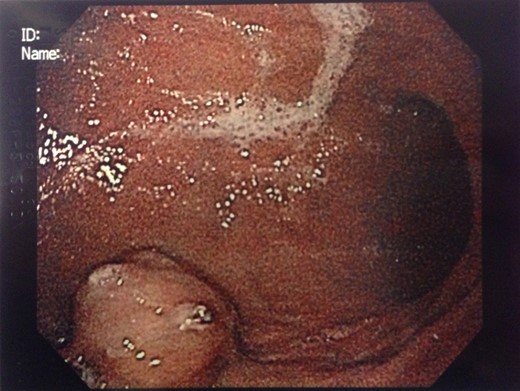

An 88-year-old female presented with 5 days of weakness and dyspnea, severe anemia (hemoglobin of 46 g/l), and no evidence of bleeding on history. Physical examination was remarkable for a blood pressure of 83/48, and black stool on rectal examination. Endoscopy demonstrated a 4-cm submucosal mass in the distal body of the stomach. The mass had central ulceration and a visible vessel, not actively bleeding. The presumptive diagnosis was GIST. CT demonstrated a 2.5 × 1.9 cm well-circumscribed, partially exophytic, arterially enhancing lesion. She underwent wedge resection of the greater curvature. She was discharged home on postoperative day 3 without complication. Pathology found a lobulated tumor composed of glomus cells in the submucosa and muscularis propria. The cells were positive for α-smooth muscle actin, caldesmon and vimentin. There was focal positivity for synaptophysin and CD34. These are consistent with a GT.

Endoscopic findings of gastric GTs are that of a submucosal mass, typically in the antrum or distal body, with either normal mucosa or ulceration [3, 4] (Fig. 1). CT shows a well-defined submucosal tumor with a clear margin, strong enhancement in the arterial phase, and prolonged enhancement in the delayed phase [4, 5] (Fig. 2). Often confused with GIST, the distinguishing features are that the density of GISTs is lower than that of GTs, and GISTs do not exhibit prolonged enhancement in the delayed phase [5]. On EUS, the GT is found in the fourth endosonographic layer, with a heterogeneous appearance. In one small study of seven gastric GTs, six demonstrated the characteristic ‘peripheral halo’ sign around the tumor [5].